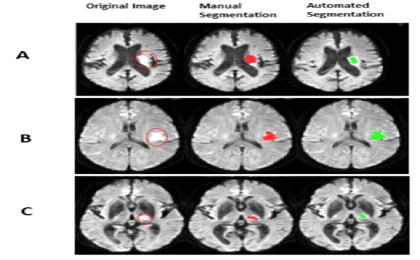

Đột quỵ là một trong những căn bệnh khó dự đoán. Người bệnh phải đối mặt với nguy cơ tử vong hoặc bị tàn tật vĩnh viễn. Điều quan trọng là phải đánh giá vị trí của đột quỵ trong não và chẩn đoán mức độ nghiêm trọng của tình trạng bệnh nhân. Và đó là lý do tại sao các bác sĩ X quang thực hiện phân đoạn tổn thương thủ công đột quỵ do thiếu máu cục bộ cấp tính.